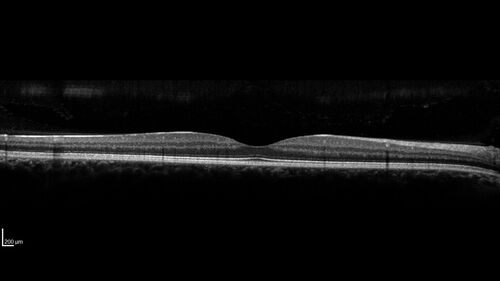

Small choroidal melanoma

28 year old man Serial images suggested that the lesion is growing

OD: sc20/16

OS: sc20/40+2

IOP: TP: OD:19 OS:16